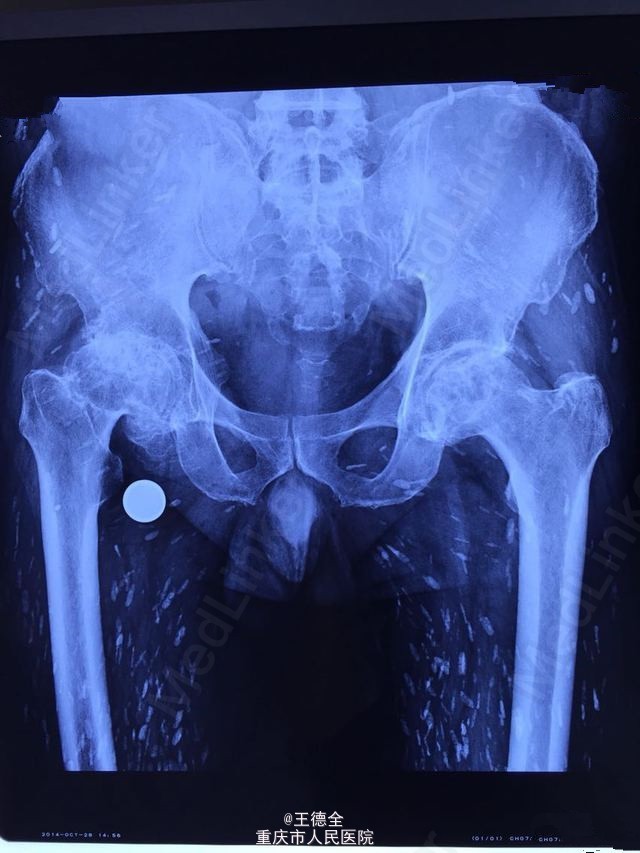

【密集恐惧症慎入】囊虫病感染+双髋置换

患者因囊虫病大剂量激素治疗后股骨头坏死,施行双髋关节置换 。